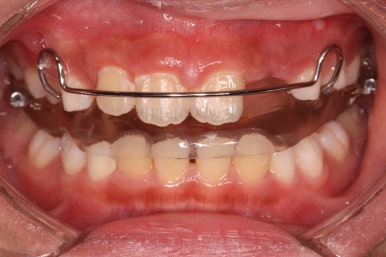

입안에 착용한 장치는 식사시간 제외 20시간 이상 사용이 추천되는 액티베이터라는 장치입니다.

이 장치는 성장이 부족한 아래턱을 앞으로 내밀어주게 되는 장치입니다.

또 다른 장치를 함께 사용해 주었는데요.

머리에 착용하는 헤드기어라는 장치입니다. 이 장치는 잘 때 위주로 해서 12시간 가량을 사용하게 됩니다.

이 환자분은 위턱이 크고 + 아래턱이 작은 즉, 위턱과 아래턱의 복합ㅈ거인 문제가 있었던 케이스였어서 각각에 대한 치료를 동시에 진행한거죠.

헤드기어는 과잉성장이 있는 위턱의 성장을 억제하고 가능한 범위에서 약간 뒤로 당겨주는 장치입니다.